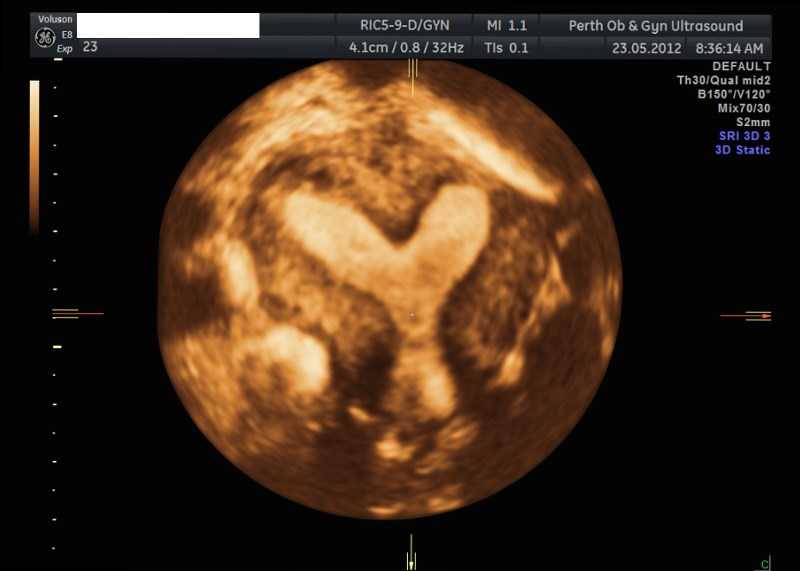

From pogu.com.au

Pelvic Ultrasound POGU What Is A 3D Pelvic Ultrasound An ultrasound scan is a test that uses high frequency soundwaves (that you can’t hear) to create an image of the inside of your body. Pelvic ultrasound scans are valuable diagnostic tools used to evaluate organs within the pelvic area, such as the uterus, ovaries, bladder, and. Pelvic ultrasound uses sound waves to create images of the reproductive organs. What. What Is A 3D Pelvic Ultrasound.

Pelvic Ultrasound POGU What Is A 3D Pelvic Ultrasound Pelvic ultrasound uses sound waves to create images of the reproductive organs. An ultrasound scan is a test that uses high frequency soundwaves (that you can’t hear) to create an image of the inside of your body. Pelvic ultrasound scans are valuable diagnostic tools used to evaluate organs within the pelvic area, such as the uterus, ovaries, bladder, and. A. What Is A 3D Pelvic Ultrasound.

Pelvic Ultrasound POGU What Is A 3D Pelvic Ultrasound Pelvic ultrasound scans are valuable diagnostic tools used to evaluate organs within the pelvic area, such as the uterus, ovaries, bladder, and. Pelvic ultrasound uses sound waves to create images of the reproductive organs. What is a 3d pelvic ultrasound? An ultrasound scan is a test that uses high frequency soundwaves (that you can’t hear) to create an image of. What Is A 3D Pelvic Ultrasound.

Pelvic Ultrasound POGU What Is A 3D Pelvic Ultrasound A pelvic ultrasound is an examination used to investigate your uterus (womb), the endometrium (the lining of the womb) and the ovaries. An ultrasound scan is a test that uses high frequency soundwaves (that you can’t hear) to create an image of the inside of your body. What is a 3d pelvic ultrasound? Pelvic ultrasound scans are valuable diagnostic tools. What Is A 3D Pelvic Ultrasound.